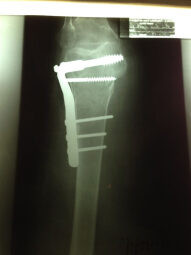

Fractura de Femur Distal